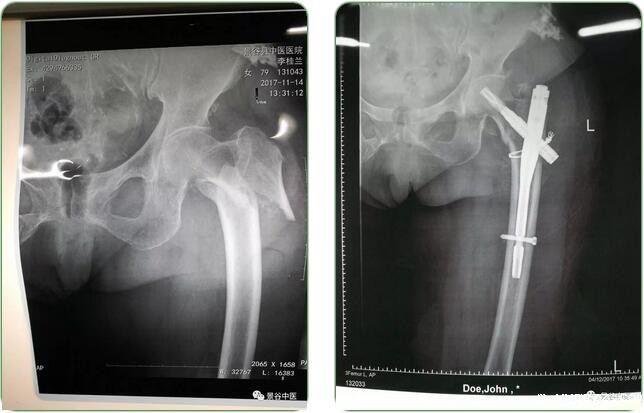

2017年9月26日,在我院外科、麻醉科全科医护人员共同努力下,开展我院第一例PFN手术治疗(股骨转子间骨折切开复位嘎玛螺旋髓内钉内固定),术后患者病情恢复较好,摄片复位好,固定可靠,术后7天可以下床扶拐行走,术后两周拆线,并办理出院。目前我院外科共开展此类手术8例,均获得满意疗效。

股骨转子间骨折多数病例为老年患者,因老年人骨质疏松,愈合差,保守治疗基本无效果,且不能下床活动,容易发生褥疮、肺部感染等并发症,严重可导致病人死亡。以往我院未开展此类手术,病人基本转往上级医院治疗。目前,我院开展此类手术,患者可以就近治疗,减轻患者经济负担,同时方便了家属护理。我院开展的PFNA手术方式较解剖钢板可靠,患者能够早期下床活动,减轻病人褥疮、肺部感染几率,提高患者的生存能力,消除了应用解剖板容易发生术后钢板断裂所引发的医疗纠纷。